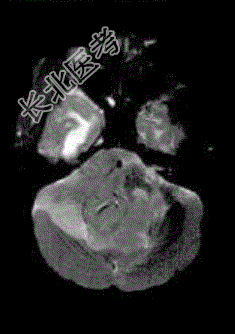

- 单项选择题成年男性患者,头痛、头晕、恶心, 病程2年余,结合影像图像选择最可能的诊断

A、星形细胞瘤

B、畸胎瘤

C、脑膜瘤

D、室管膜瘤

E、胶质瘤